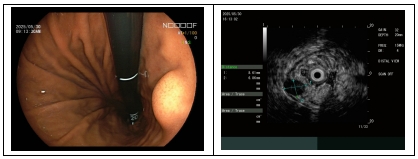

病房设有住院病区及内镜诊疗区,内镜诊疗区拥有先进的电子胃肠镜、超声内镜、氩气刀、幽门螺旋杆菌检测仪等设备。

主要诊治消化道出血、反流性食管炎、急慢性胃肠炎、消化性溃疡、胰腺炎、肝硬化等疾病,运用中西医结合诊治,注重中医药辩证施治,具有良好疗效。开展普通及无痛胃肠镜及胃肠镜下息肉切除术、EMR术(内镜下黏膜切除术)、ESD术(内镜下黏膜剥离术)、内镜下异物取出术、内镜下止血术、内镜下食管胃底静脉曲张治疗、消化道早癌筛查、超声内镜检查及幽门螺旋杆菌检测等。

5.超声内镜检查